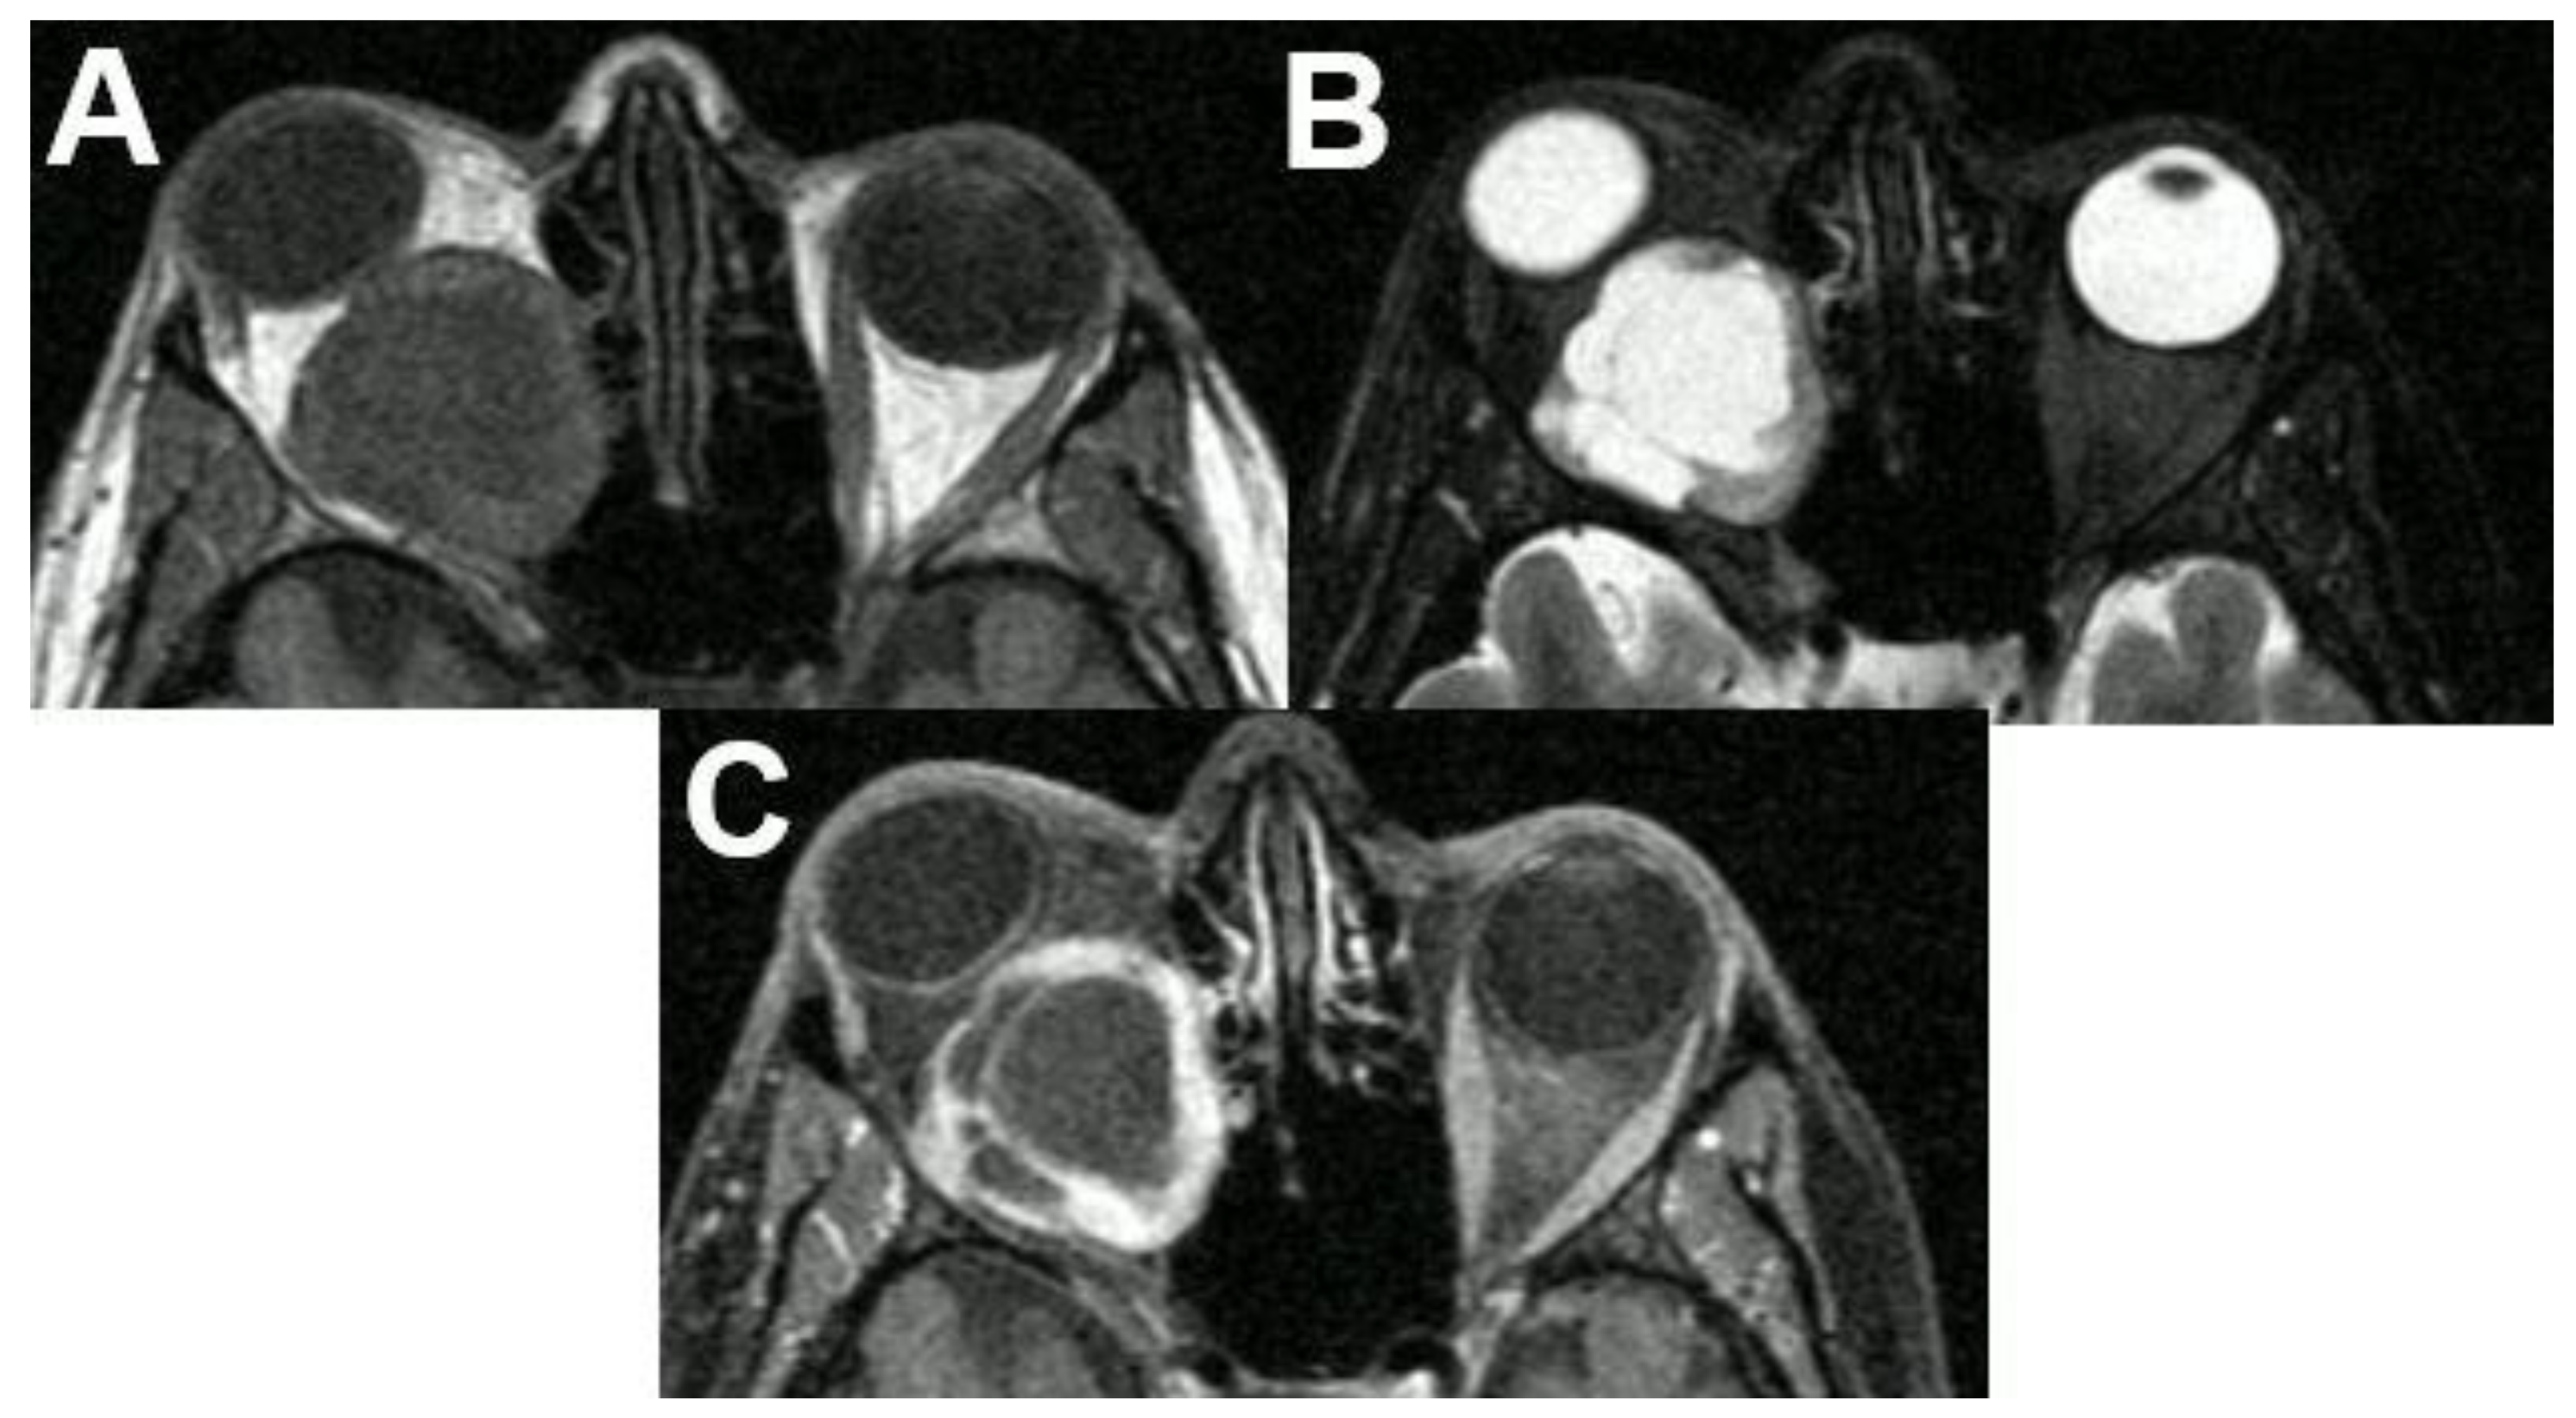

3.6. Masses with Involvement of Different Parts of the Orbit

3.6.1. Metastasis

3.6.2. Rhabdomyosarcoma